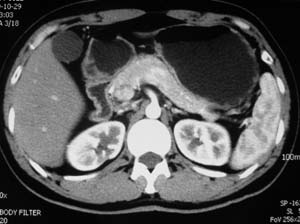

以下是引用子期在2010-3-19 20:47:00的发言:[br]血管畸形的ct增强应该有明显强化,本例并不相符合。本例双肾局部的略低密度影,累及肾盂,局部皮质明显变薄、内陷,增强扫描有轻度的强化,应考虑为炎性病变,患者为年轻男性,累及双肾的感染以结核较常见,可以没有明显的临床症状,尿中有时候也并不能查出什么;肾脓肿常有明显感染中毒症状,本例不符,另外一般的肾盂肾炎或肾小球肾炎通过小便就可确诊,其它还不能排除的是黄色肉芽肿性肾盂肾炎,然而单凭ct一般也很难鉴别。